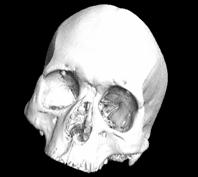

发挥了重要作用。CT的临床应用非常广泛,包括头颈部疾病、胸部疾病、心脏及大血管的CT检查、腹部疾病检查等等。在工业上可以检测高密度和大尺寸物体、多孔材料或微米级的电路元件,检测内容包含内部缺陷、杂质分布、密度变化、装配结构、尺寸测量等。

心脏成像 SiC泡沫陶瓷 现代人头骨